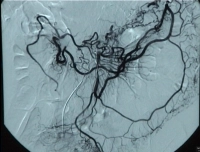

Clipe de vídeo: Oclusão da AMS próxima à sua origem com oclusão do tronco celíaco